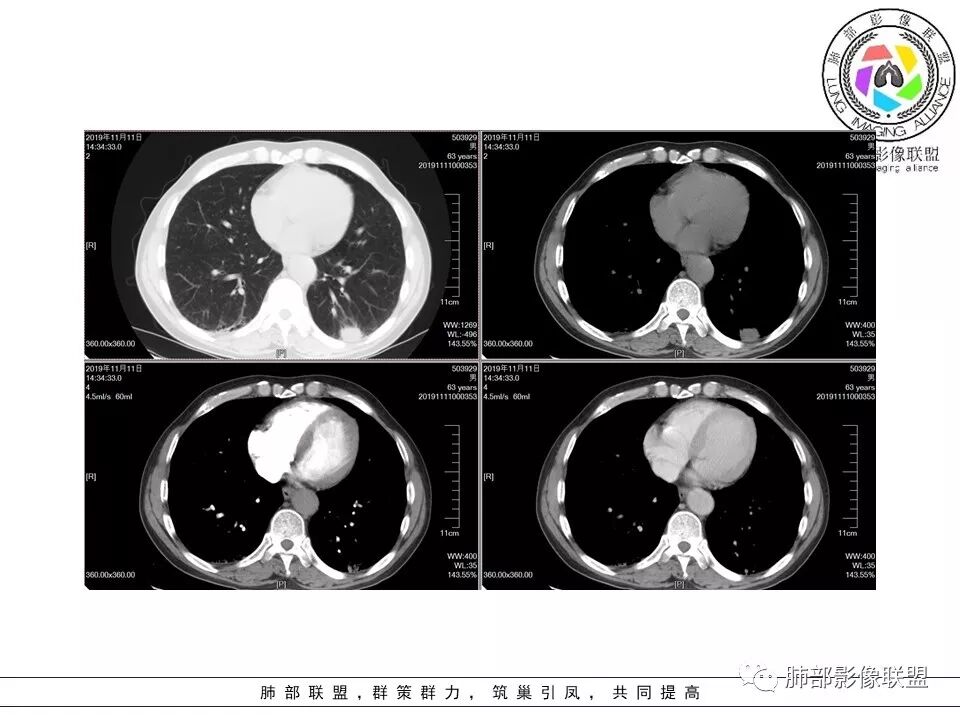

大雄:老年男性,有类风湿病史,长期服用激素,无阳性主诉CT示右肺上叶后段及左肺下叶基底段胸膜下多结节影,境界清晰,边缘毛糙,整体收缩,长轴与胸膜平行,增强扫描轻中度均匀强化。考虑炎性病变,建议查隐球荚膜多糖滴度试验

晕晕菜:患者中老年男性,体检发现肺部占位。既往既往有类风湿关节炎,长期口服激素胸CT:间隔旁肺气肿,右肺上叶后段胸膜下病变,与胸膜宽基底相连,局部胸膜明显增厚,病灶内可见空洞,病灶周围有散在卫星灶。左肺下叶背段胸膜下实变,病灶边界清楚,与长轴与胸膜平行,病灶周围可见软毛刺,纵隔窗可见病灶与胸膜呈糊墙征。 总体考虑良性病变。右上:结核?左下:隐球菌?

没意见:老年男性,明确有风免疾病背景,长期激素治疗,CT:双肺下叶外周多发结节,大部分宽基底胸膜相连,长轴垂直支气管,刀切平直,密度较为均匀,近心端空洞,强化程度目测略低,下肺背侧网格、磨玻璃、小蜂窝,考虑炎性结节,至于是感染还是风湿结节难度较大,需要结合临床来进一步确认

小赵:老年男性,类风湿及长期服药史。胸部CT所见右肺上叶及左肺下叶胸膜下多发病灶,右肺上叶病灶内见空洞及液平面,内壁光滑,周围散在条索及小结节样卫星灶,邻近胸膜增厚,增强扫描病灶轻度强化。左肺下叶病灶长轴平行于胸膜,周围见边界不清磨玻璃密度影,与邻近胸膜成糊墙改变。增强扫描病变成不均匀明显强化,内见强化血管影。诊断一元考虑双肺炎性病变,隐球菌可能。二元考虑右肺上叶结核,左肺下叶隐球菌感染,粘液腺癌待排。

俞丽:双侧胸膜下结节及斑片影,与胸膜平行,大部分周围有晕症,边界模糊,胸膜下脂肪间隙存在,边缘平直,有强化。老年女性,良性,考虑隐球菌感染

菲菲菲:男,63,体检发现肺占位,既往类风湿性关节炎13年,双肺胸膜下多发斑片及结节影,右肺下叶病灶内见偏心性小空洞形成,周围有卫星灶,胸膜增厚,左肺下叶病灶轻度强化,纵隔内无肿大淋巴结,考虑炎性病变。隐球菌鉴别结核

一米阳光:双肺胸膜下多发结节病影,小结节融合,病灶与胸膜面平行,垂直支气管,边缘模糊,晕征,支气管进入堵塞,内见小空洞,增强均匀强化。结合病史,有类风湿病史,考虑炎性肉芽肿,隐球菌感染。鉴别,结核建议,穿刺,隐球荚膜抗原检查

雪上一枝蒿(陈显静):右上肺病灶,似见周边卫星灶,空洞朝向肺门,考虑炎性病变,结核?左下肺结节长轴平行胸膜,强化后似有低密度影,隐球菌?二元论?。

破风5:胸部CT:右上叶胸膜下病变,与胸膜宽基底相连,累及胸膜,病灶内可见空洞,洞壁光滑,病灶周围有散在卫星灶。有类风湿激素口服历史,结核首先考虑。左肺下叶背段胸膜下实变,病灶边界清楚,与长轴与胸膜平行,血管伸入,纵隔窗可见糊墙征。考虑良性病变,隐球?总体,右上肺结核,左下肺隐球,CTD-ILD

流心明智:患者,老年男性,既往有类风湿关节炎,长期口服激素史。胸CT:间隔旁肺气肿,右肺上叶后段胸膜下病变,与胸膜宽基底相连,局部胸膜增厚,病灶内向肺门侧空洞,病灶周围卫星灶。考虑炎性病灶。左肺下叶胸膜下气肿背景边缘实变、边界清楚、有膨隆、滋养血管征,软毛刺、多结节融合、糊墙征。 总体考虑:良性病变,右上:结核?左下:隐球菌?左下鉴别Ca。

傅昌瑜:男,63,体检发现肺占位,既往类风湿性关节炎13年,RF升高,右下肺胸膜下结节,边缘多发斑片,右肺下叶病灶内见偏心性小空洞形成,相应层面胸膜增厚,左肺下叶两个结节,上面大点的结节位于胸膜下,似有支气管进入后截断,病灶轻度强化,病灶内见坏死区,纵隔内无肿大淋巴结。肺内病灶似乎不怎么类似,隐球菌应该是兄弟同心。肺内病灶考虑肉芽肿性病灶,有长期口服糖皮质激素史,首先考虑奴卡可能,鉴别隐球菌及结核这个妖怪。类风湿结节没有见过。

初学者:支持。。。类风湿关节炎,那么肺内表现的是间质性肺炎,这个没有问题。现在就是看这些结节和团块是什么。患者有哪些危险因素:1.类风湿关节炎:类风湿结节 2.因为激素治疗,熊大说激素就是小艾滋,那么会容易得得:隐球菌,结核,PCP等等。3.间质性肺炎本身就容易发生肿瘤。所以目前我们需要考虑得三个方向:类风湿结节,肉芽肿性炎,或肿瘤。三者鉴别